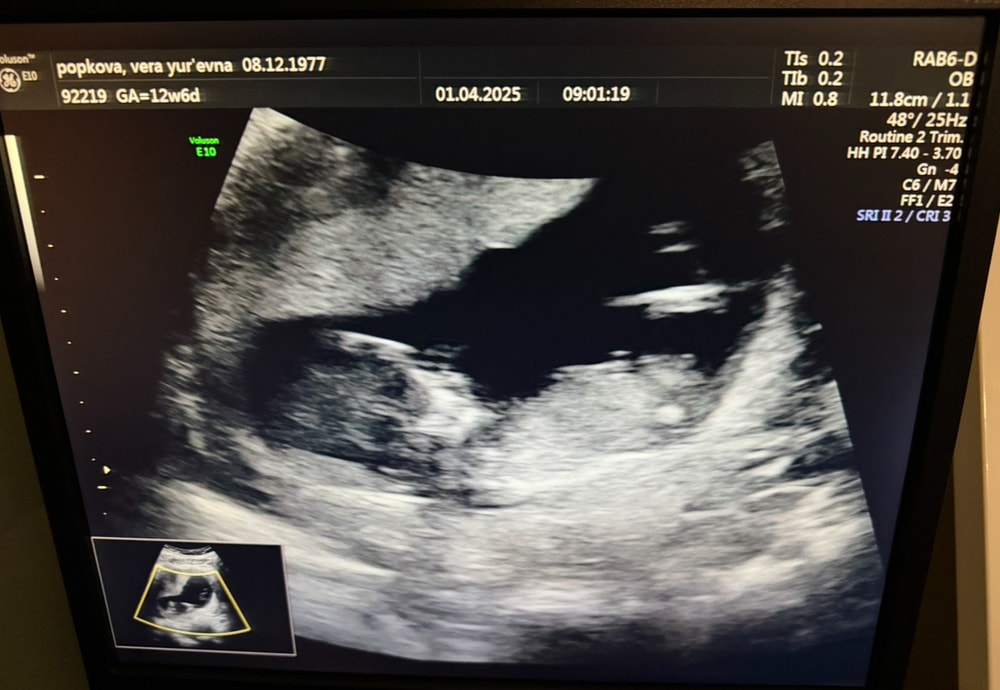

Прошла первый скрининг, 12 недель 3 дня

Алина, я врачей слушаю, а врачи сказали, что риск низкий. Толщина воротникового пространства 1,42. Я же на второй скрининг пойду и на третий. Зачем мне пытаются здесь навязать что у меня высокий риск, если по результатам НИПТ и результатам сдачи крови в день скрининга пишут, что риск низкий??

Хитрая Лиса, у меня срок 12,3 , врач сказал, что все в норме и носовая кость и воротниковая зона